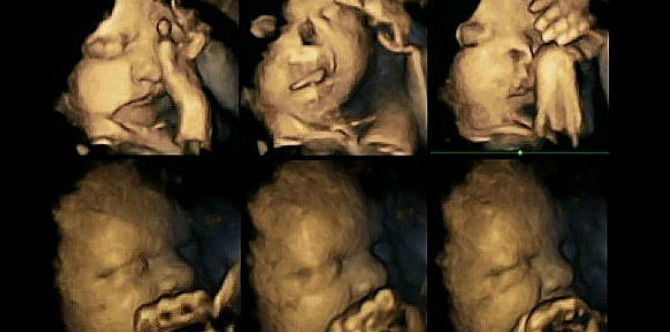

The 4D ultrasound showed two rows of images.

The image of the foetus above is grimacing; its mum smokes an average of 14 cigarettes a day. The baby below, on the other hand, appears calm. Its mother doesn’t smoke.

Movements in a foetus whose mother is a smoker (top) and a foetus whose mother is a non-smoker (below); credit Dr Nadja Reissland, Durham University